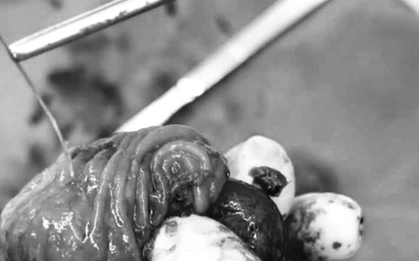

Người đàn ông 33 tuổi bỗng đau bụng dữ dội, sốt nhẹ và phản ứng thành bụng, khiến gia đình vô cùng hoảng hốt. Gia đình bệnh nhân vô cùng kinh ngạc khi biết "thủ phạm" gây ra tình trạng này.